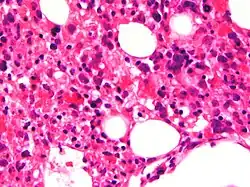

Micrograph showing red blood cells within macrophages. H&E stain. | |